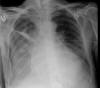

Neumonía basal.